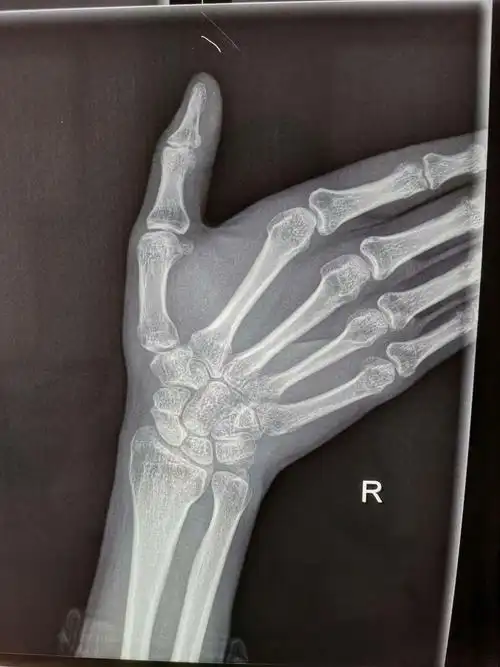

郑州市骨科医院会诊病例 腕舟骨骨折